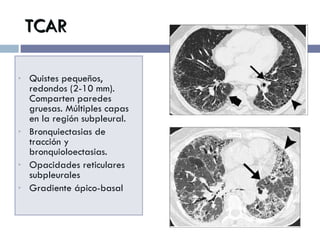

TCAR Quistes pequeños, redondos (2-10 mm). Comparten paredes gruesas. Múltiples capas en la región subpleural. Bronquiectasias de tracción y bronquioloectasias. Opacidades reticulares subpleurales Gradiente ápico-basal

Distribución Bilateral y en parches Periférico y subpleural, más prominente en los segmentos posteriores Predominantemente basal..

Otros signos radiológicos Patrón reticular irregular inter e intralobular Opacidades en vidrio despulido asociado a bronquiolectasias. Crecimiento de GL mediastinales (50-90%), más frecuente en las formas extensas.